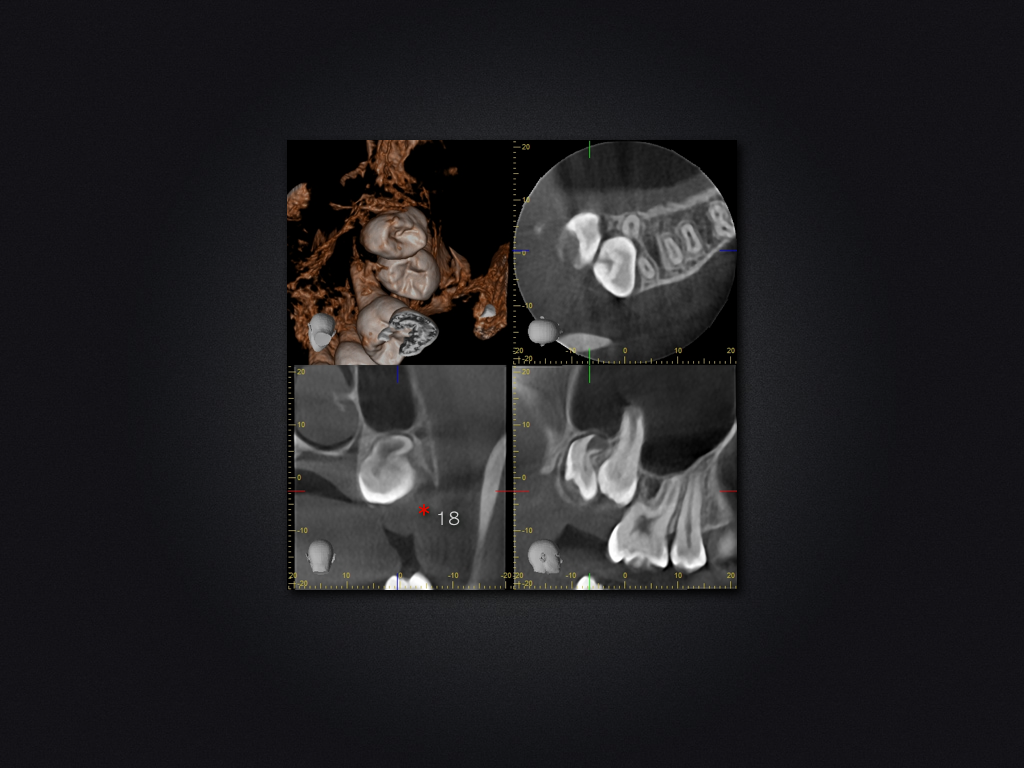

18D.004

2D vs. 3D (XXIII)